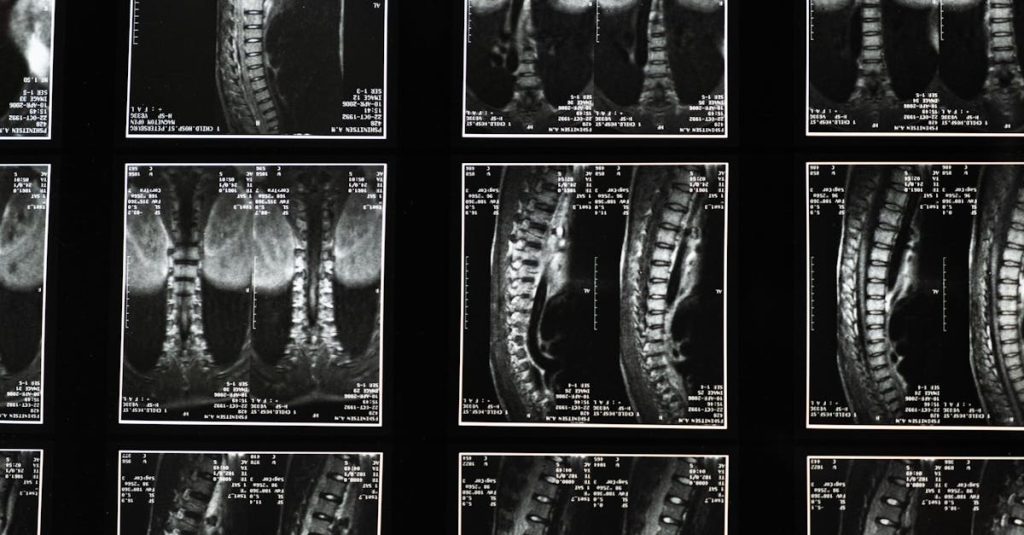

Imagerie 3D – Fournit une visualisation précise des structures vertébrales pour un traitement personnalisé.

Évaluation par imagerie

Utilisation d’images pour guider et évaluer l’efficacité des traitements.